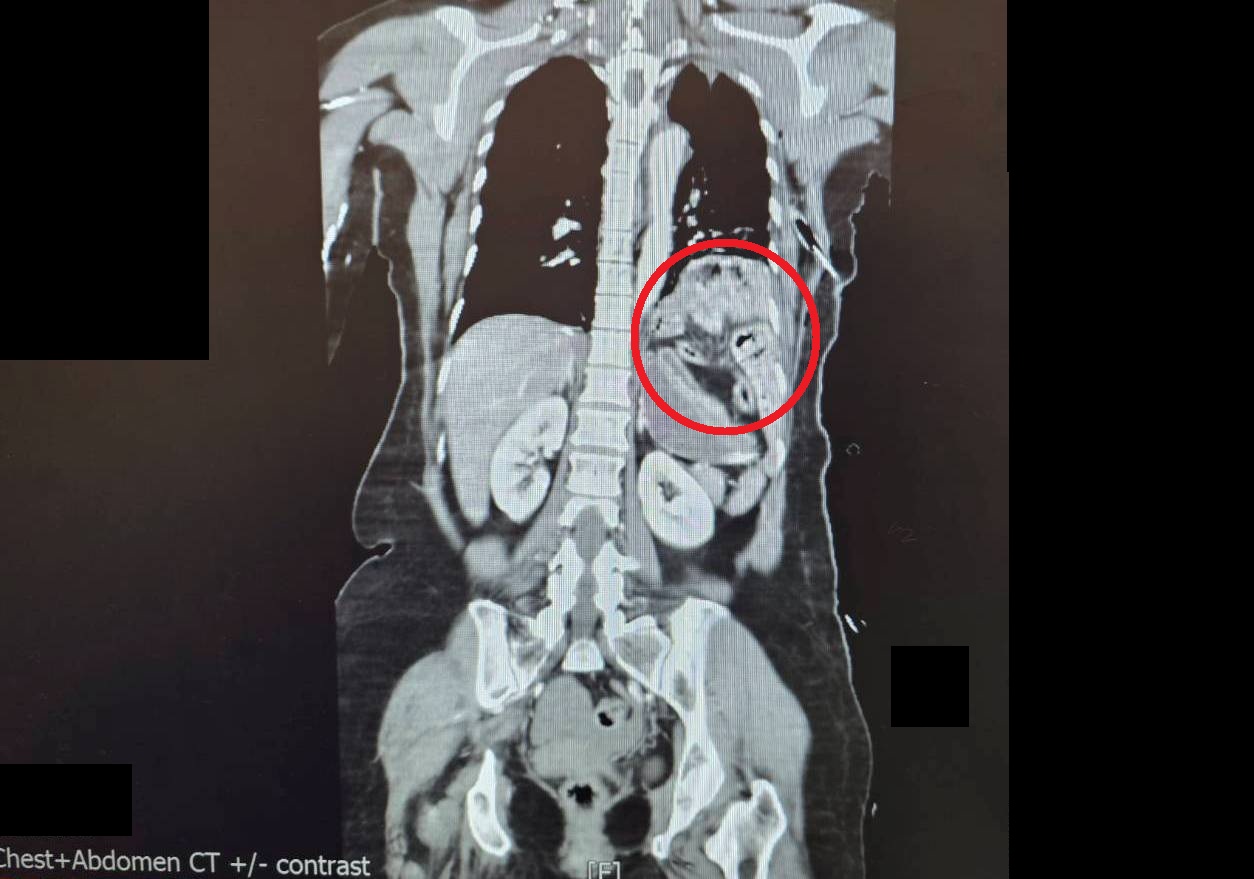

陳姓女子被送抵急診時,出現嚴重的雙側氣胸與皮下氣腫,呼吸極度困難。經全身電腦斷層掃描發現,強大的撞擊力導致她的左側橫隔膜破裂,原本應在腹腔的胃部及部分腸道,竟位移進入左側胸腔,嚴重壓迫左肺,導致肺部無法擴張。此外,檢查更發現其下腹部大量出血(腸繫膜血管破裂)、左腳踝骨折,背部還有大面積的2至3度擦燙傷,傷勢遍布全身。